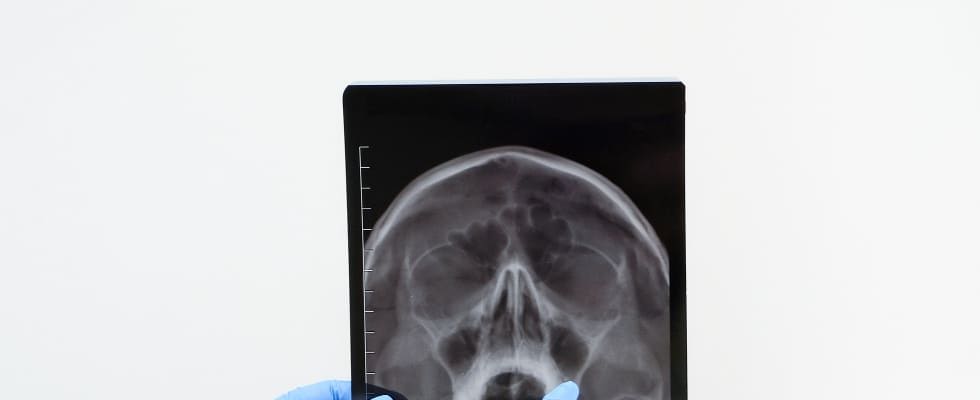

RTG zatok obocznych nosa to badanie radiologiczne, które pozwala na ocenę stanu zatok przynosowych. Wykonanie tego badania jest istotne w diagnostyce różnorodnych schorzeń zatok, takich jak zapalenie zatok, polipy, torbiele czy guzy. Dzięki RTG możliwe jest uzyskanie szczegółowych obrazów, które pomagają lekarzom w precyzyjnym określeniu przyczyny dolegliwości oraz w planowaniu odpowiedniego leczenia. Badanie to jest szybkie, bezbolesne i nieinwazyjne, co czyni je cennym narzędziem w codziennej praktyce medycznej.

Badanie RTG zatok obocznych nosa polega na wykonaniu zdjęć rentgenowskich, które pozwalają na ocenę stanu zatok przynosowych. Pacjent zostaje umieszczony w odpowiedniej pozycji, a następnie wykonywane są zdjęcia w różnych projekcjach, aby uzyskać pełny obraz zatok. Promienie rentgenowskie przechodzą przez tkanki, tworząc obrazy, które mogą ujawnić obecność stanów zapalnych, polipów, guzów czy innych nieprawidłowości. Wyniki badania są następnie analizowane przez radiologa, który dostarcza szczegółowy opis stanu zatok.